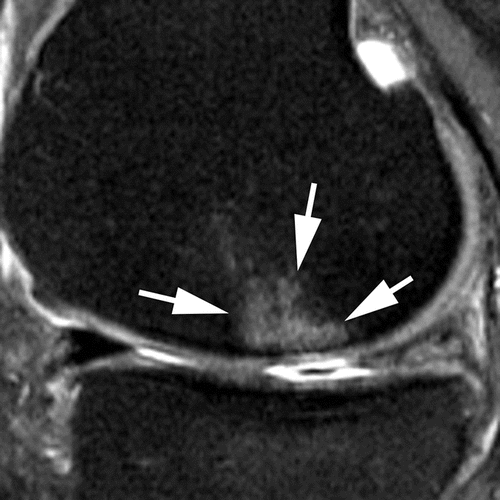

Cartilage Damage

Increased risk of replacement:

• grade 3 damage (OR 4.0)

• 2 or more subregions affected (OR 16.5)